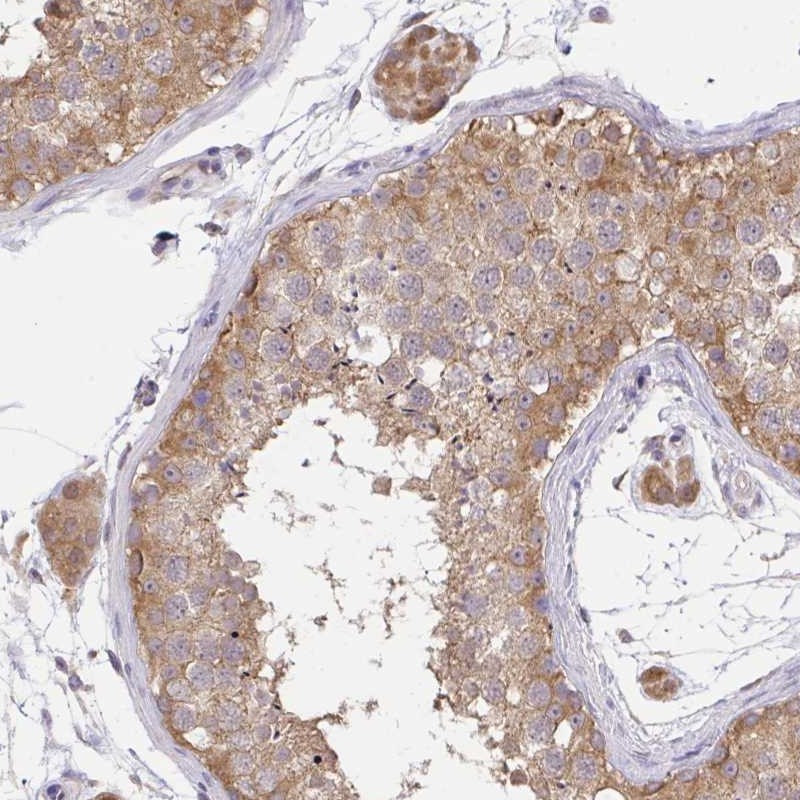

Immunohistochemical staining of human testis shows moderate cytoplasmic positivity in cells in seminiferus ducts and Leydig cells.